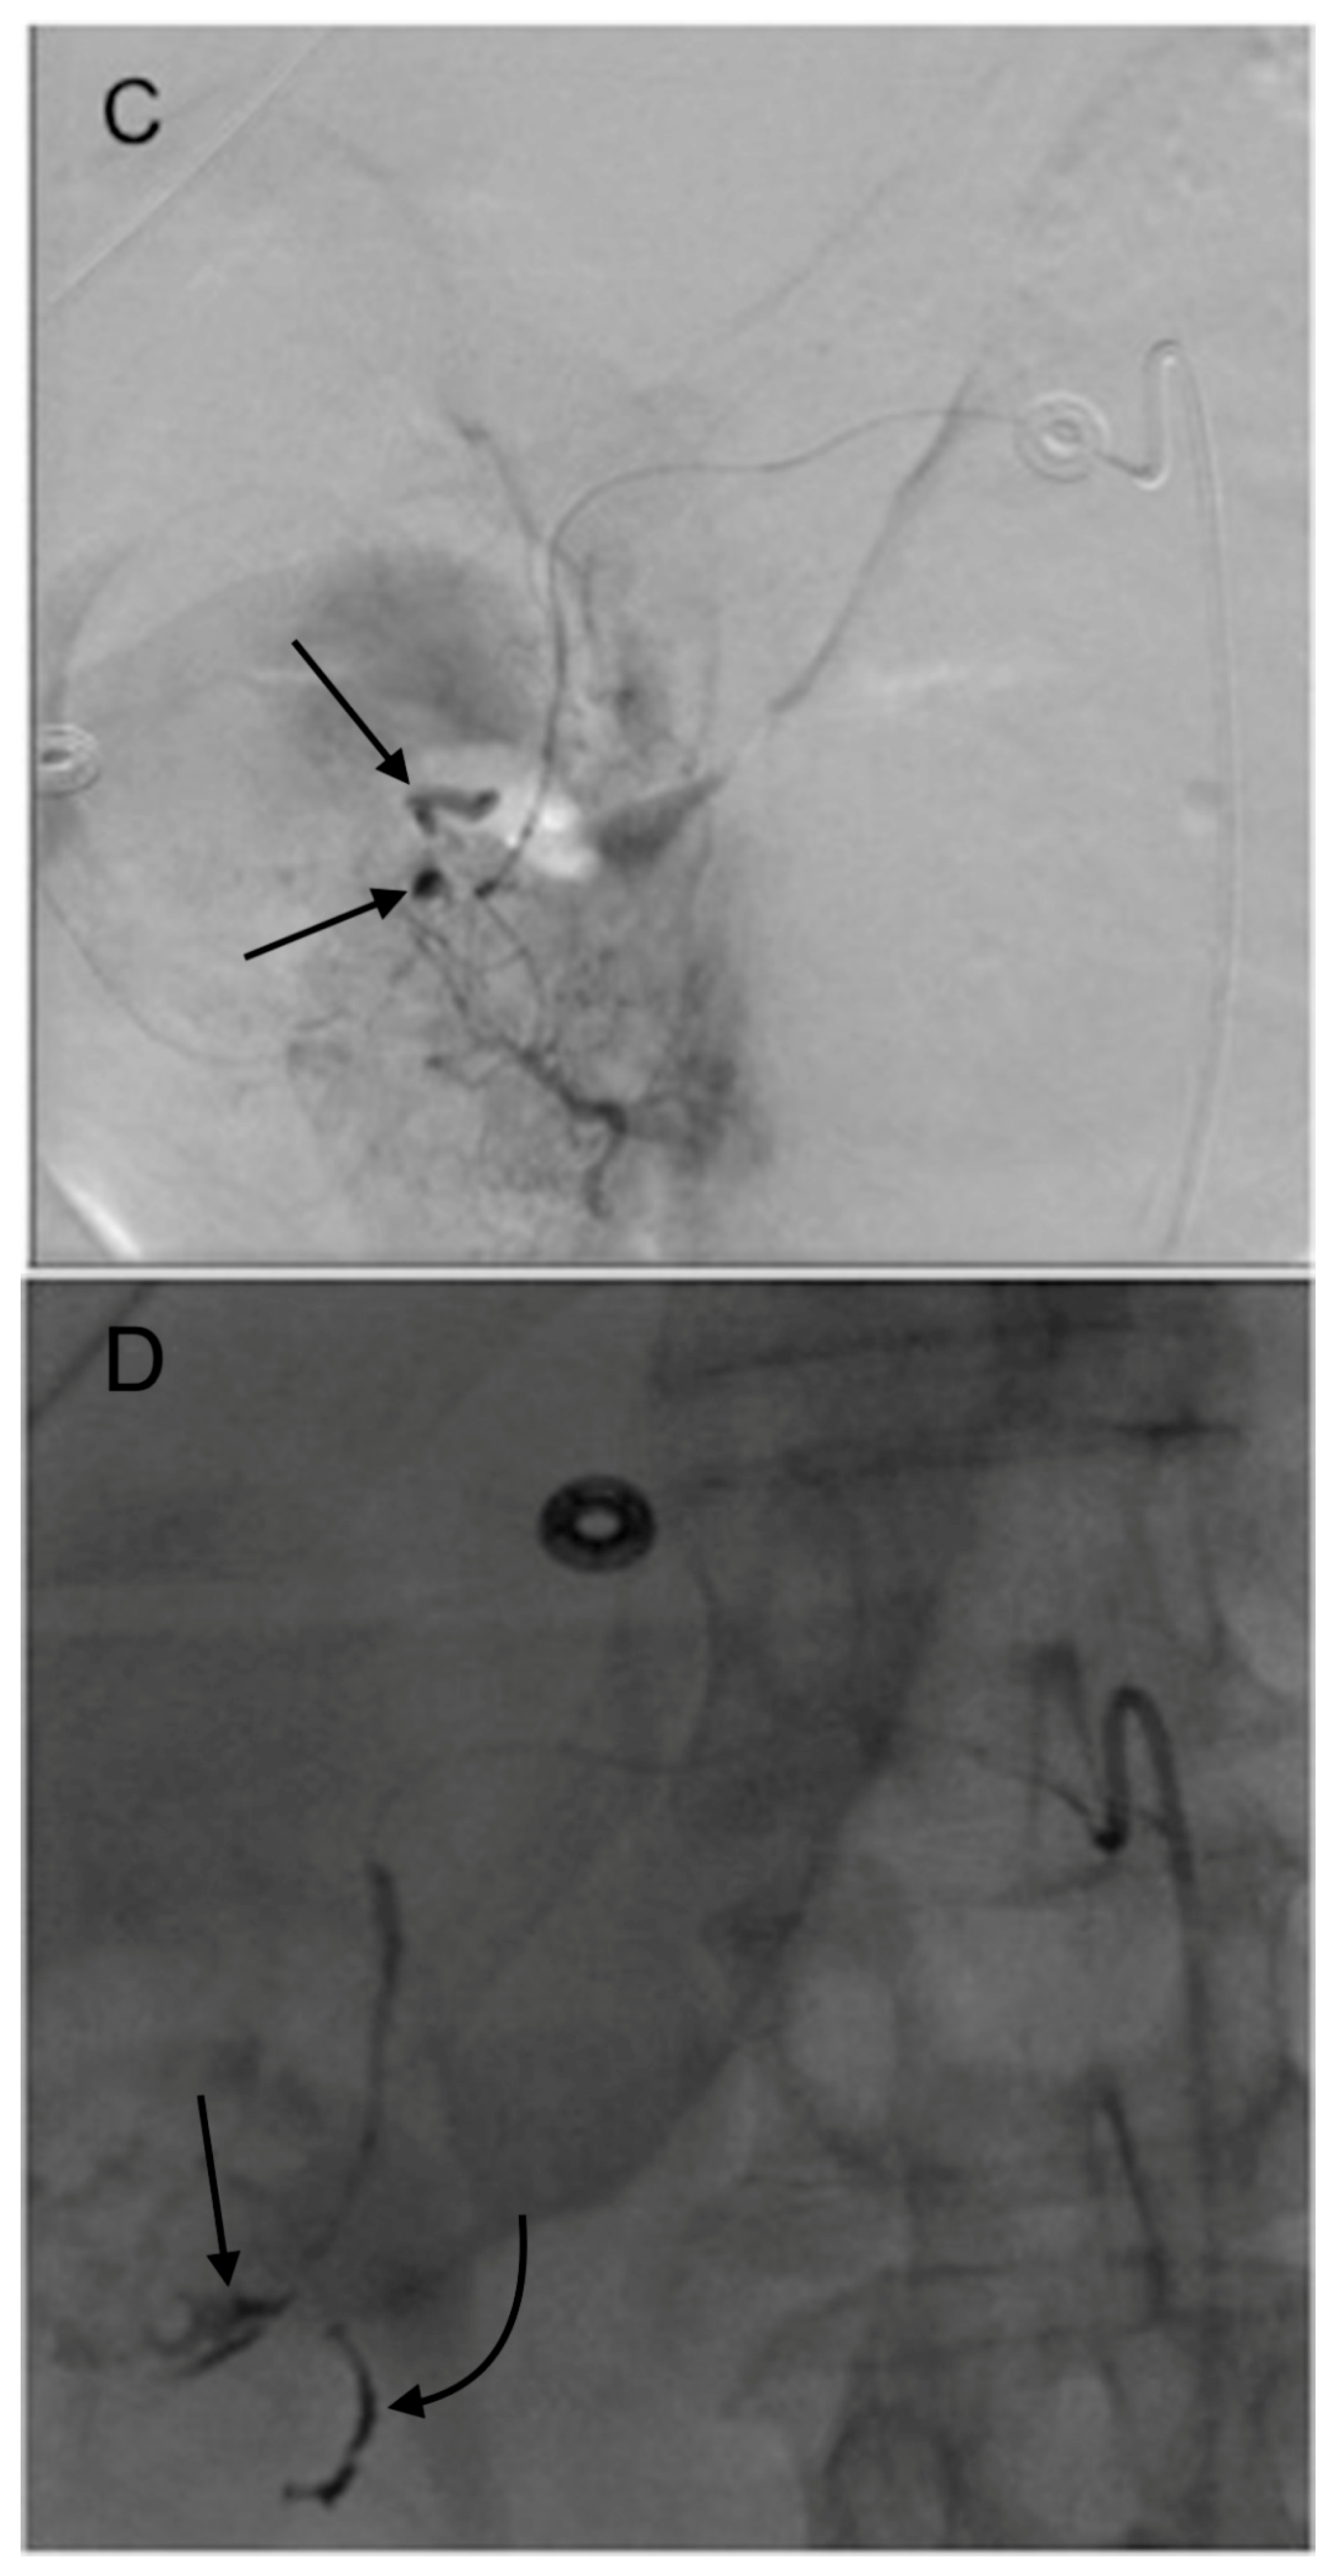

- Schelhorn, J.; Theysohn, J.; Ertle, J.; Schlaak, J.; Mueller, S.; Bockisch, A.; Lauenstein, T. Selective internal radiation therapy of hepatic tumours: Is coiling of the gastroduodenal artery always beneficial? Clin. Radiol. 2014, 69, e216–e222. [Google Scholar] [CrossRef] [PubMed]

- Petroziello, M.F.; McCann, J.W.; Gonsalves, C.F.; Eschelman, D.J.; Anne, P.R.; Sato, T.; Doyle, L.A.; Frangos, A.; Brown, D.B. Side-branch embolization before 90Y radioembolization: Rate of recanalization and new collateral development. Am. J. Roentgenol. 2011, 197, W169–W174. [Google Scholar] [CrossRef] [PubMed]

- Liu, D.M.; Salem, R.; Bui, J.T.; Courtney, A.; Barakat, O.; Sergie, Z.; Atassi, B.; Barrett, K.; Gowland, P.; Oman, B.; et al. Angiographic considerations in patients undergoing liver-directed therapy. J. Vasc. Interv. Radiol. 2005, 16, 911–935. [Google Scholar] [CrossRef] [PubMed]

- Enriquez, J.; Javadi, S.; Murthy, R.; Ensor, J., Jr.; Mahvash, A.; Abdelsalam, M.E.; Madoff, D.C.; Wallace, M.J.; Avritscher, R. Gastroduodenal artery recanalization after transcatheter fibered coil embolization for prevention of hepaticoenteric flow: Incidence and predisposing technical factors in 142 patients. Acta Radiol. 2013, 54, 790–794. [Google Scholar] [CrossRef] [PubMed]